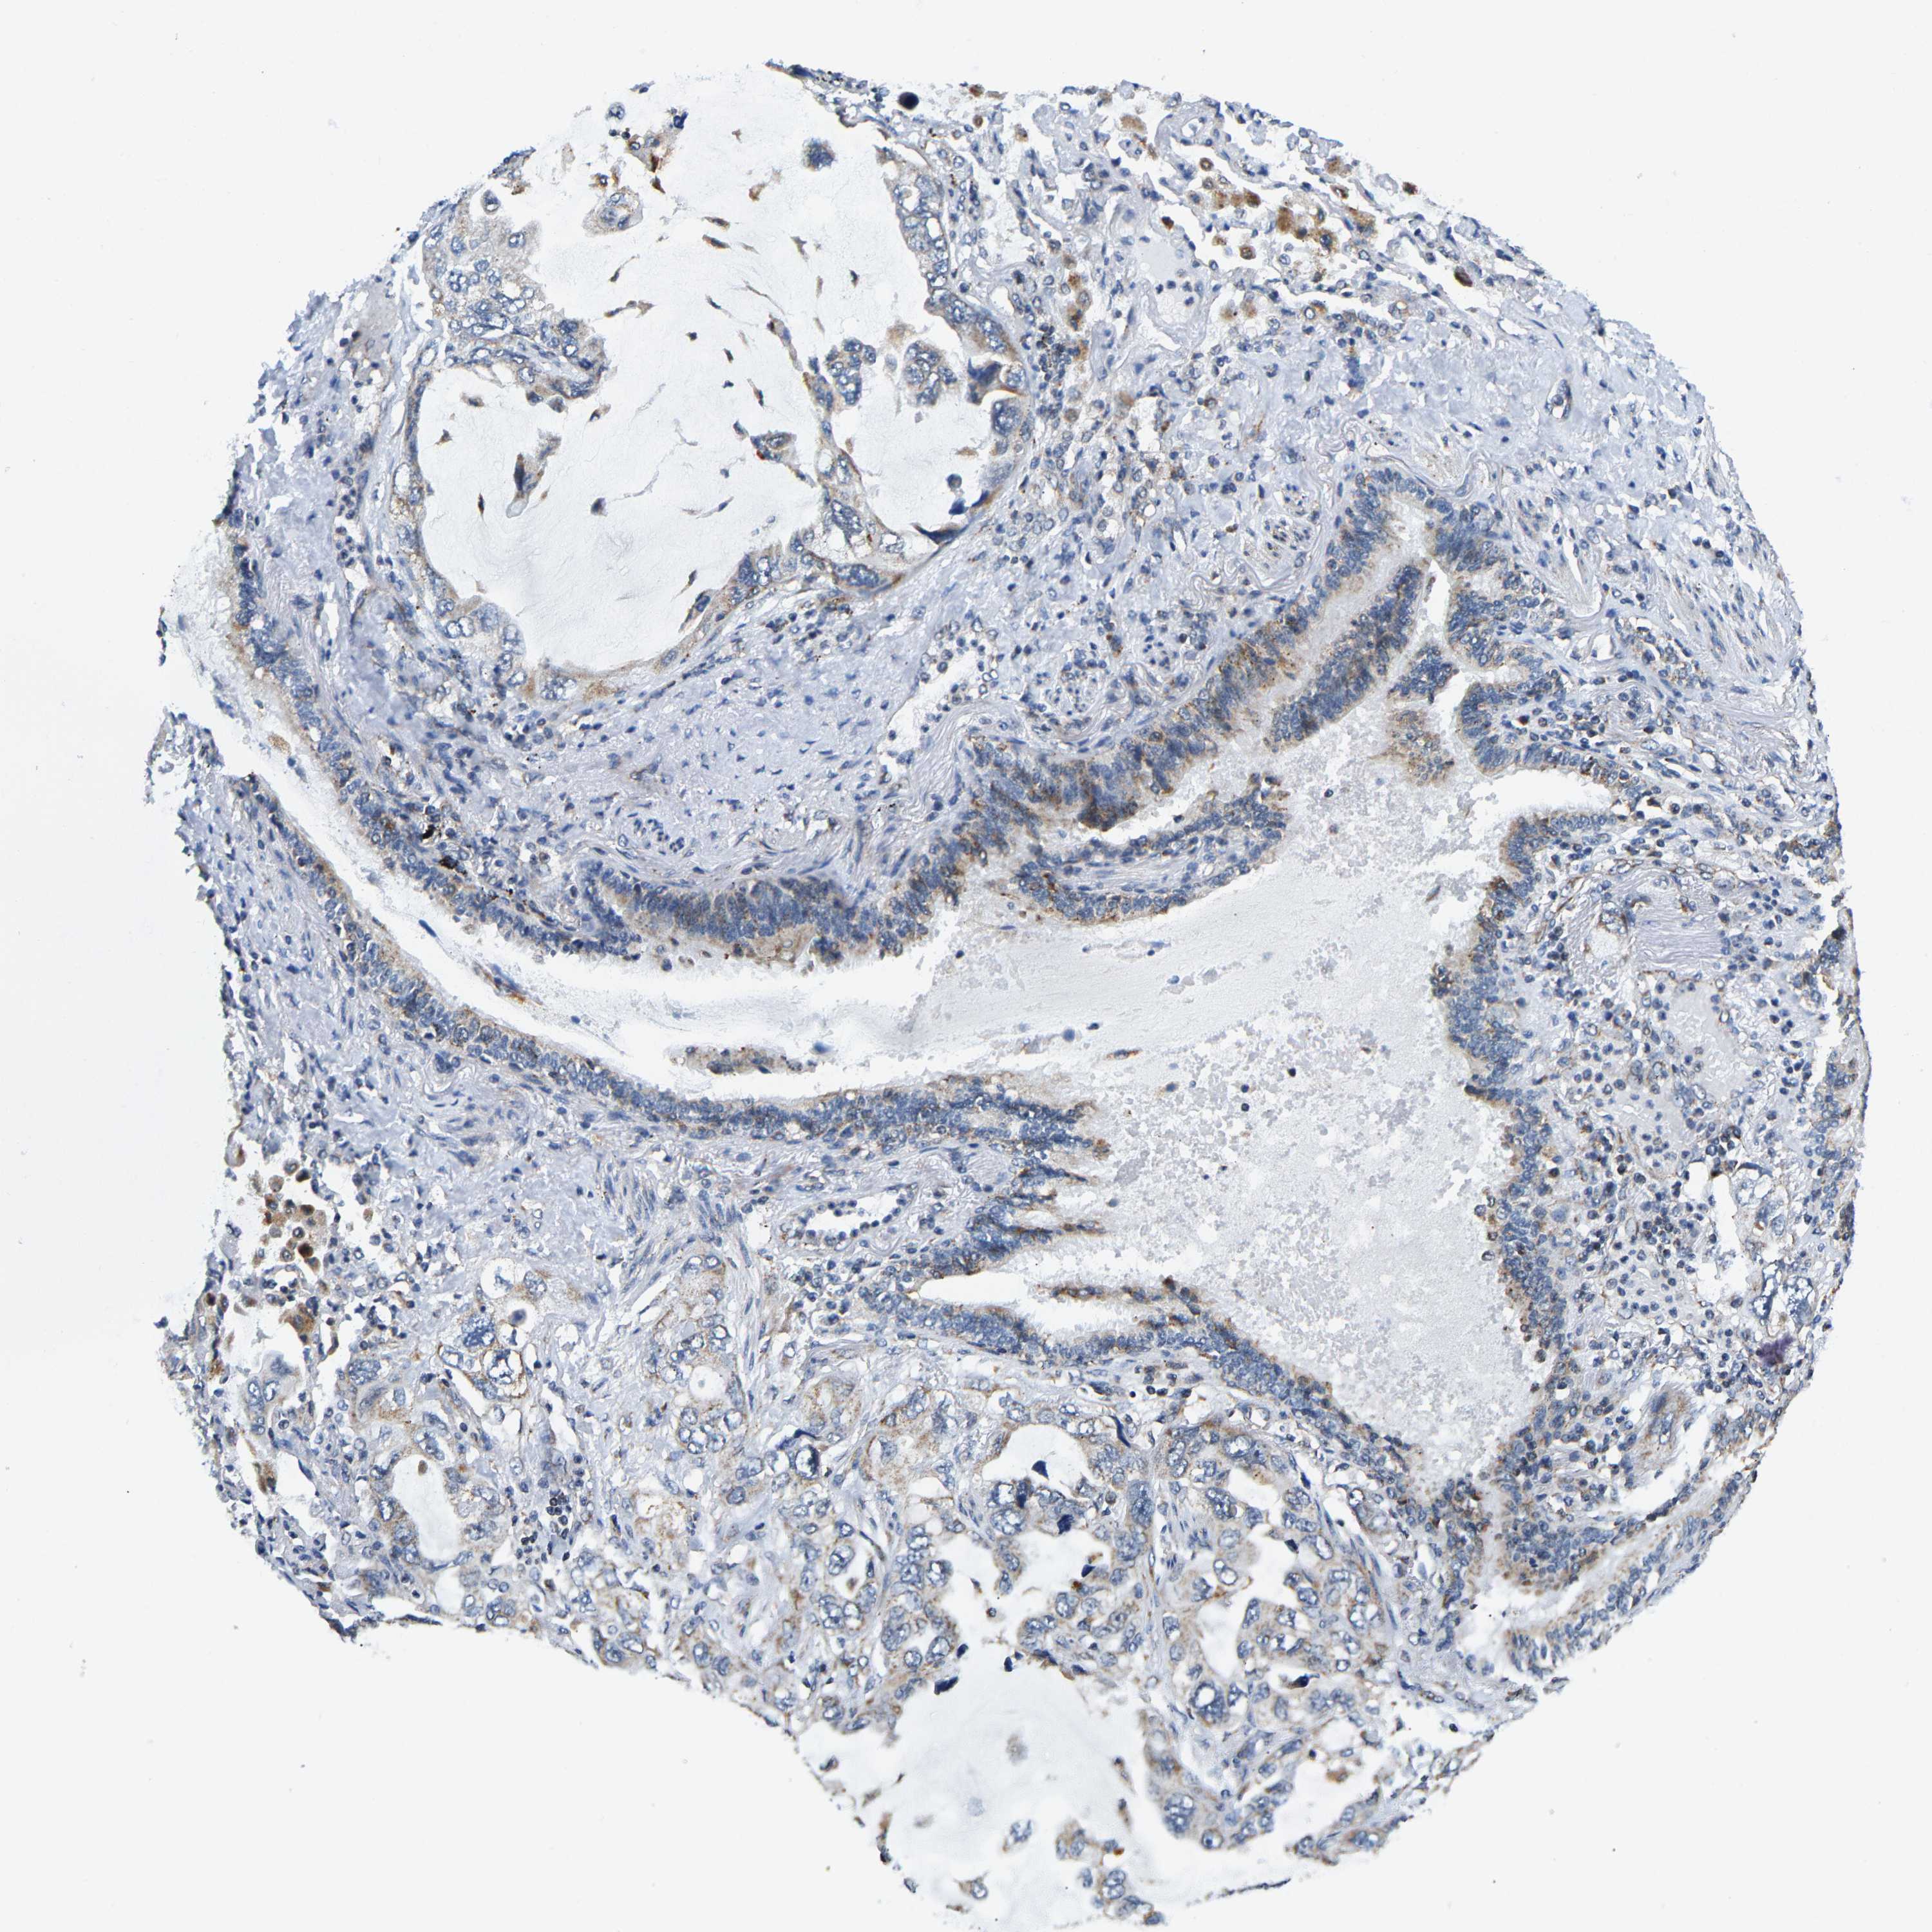

LUNG SQUAMOUS CELL CARCINOMA (TCGA) - Interactive survival scatter ploti

GIMAP7 is not prognostic in Lung Squamous Cell Carcinoma (TCGA)

: 10.79

Average pTPM 10.3

Number of samples 489